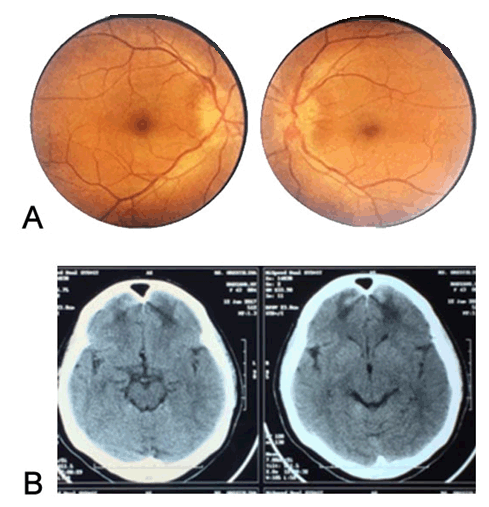

Eye examination revealed best corrected visual acuity on right eye 20/20 and 20/25 on left eye. Diplopia was mostly at distance but was occasionally noted at near. Separation of objects was horizontal. There were bilateral esodeviation with limitation in abduction corresponding to bilateral abducens nerve palsy (Figure 2). The rest of cranial nerves were normally functioned. Pupils were normal. No relative afferent pupillary defect was found. Funduscopy showed papilledema in both eyes (Figure 3A).

Head Computed Tomography (CT) scans taken one day after injury showed hematoma and cerebral contusion in the bilateral frontal area and also subarachnoid hematoma. No data except expertation from the radiologist. Second head CT-scan was taken after two weeks after injury that showed resolution of hematoma with focal edema remain in frontal area (Figure 3B).

Figure 3: Funduscopy shows papilledema in both eyes. (B) Second head Computed Tomography (CT) scan that taken 2 weeks after injury shows resolution of hematoma but still some area with focal edema in frontal lobe (white arrow).